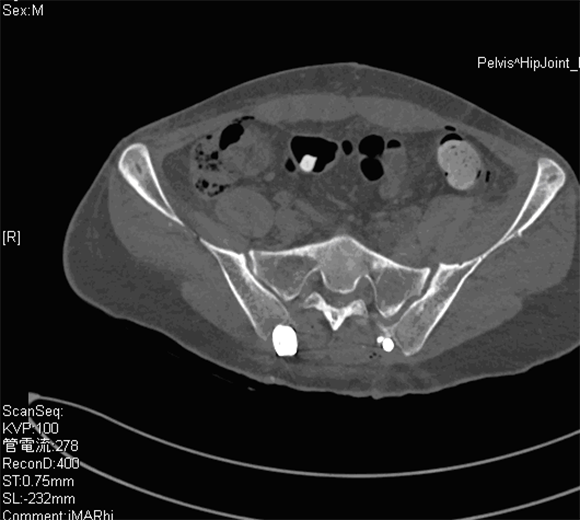

特に重度の脊椎脊髄損傷や骨盤外傷など一般病院ではなかなか見られない疾患も多数経験することが可能となります。脊椎骨盤外傷では近年低侵襲手術が全国で行われており、我々も独自の方法にて良好な成績をおさめています。一例を紹介します。

骨盤外傷症例 仙腸関節の脱臼が見られる

低侵襲に小皮切にて行った。 術後写真

左:術前 右:術後 良好な整復位が得られている。